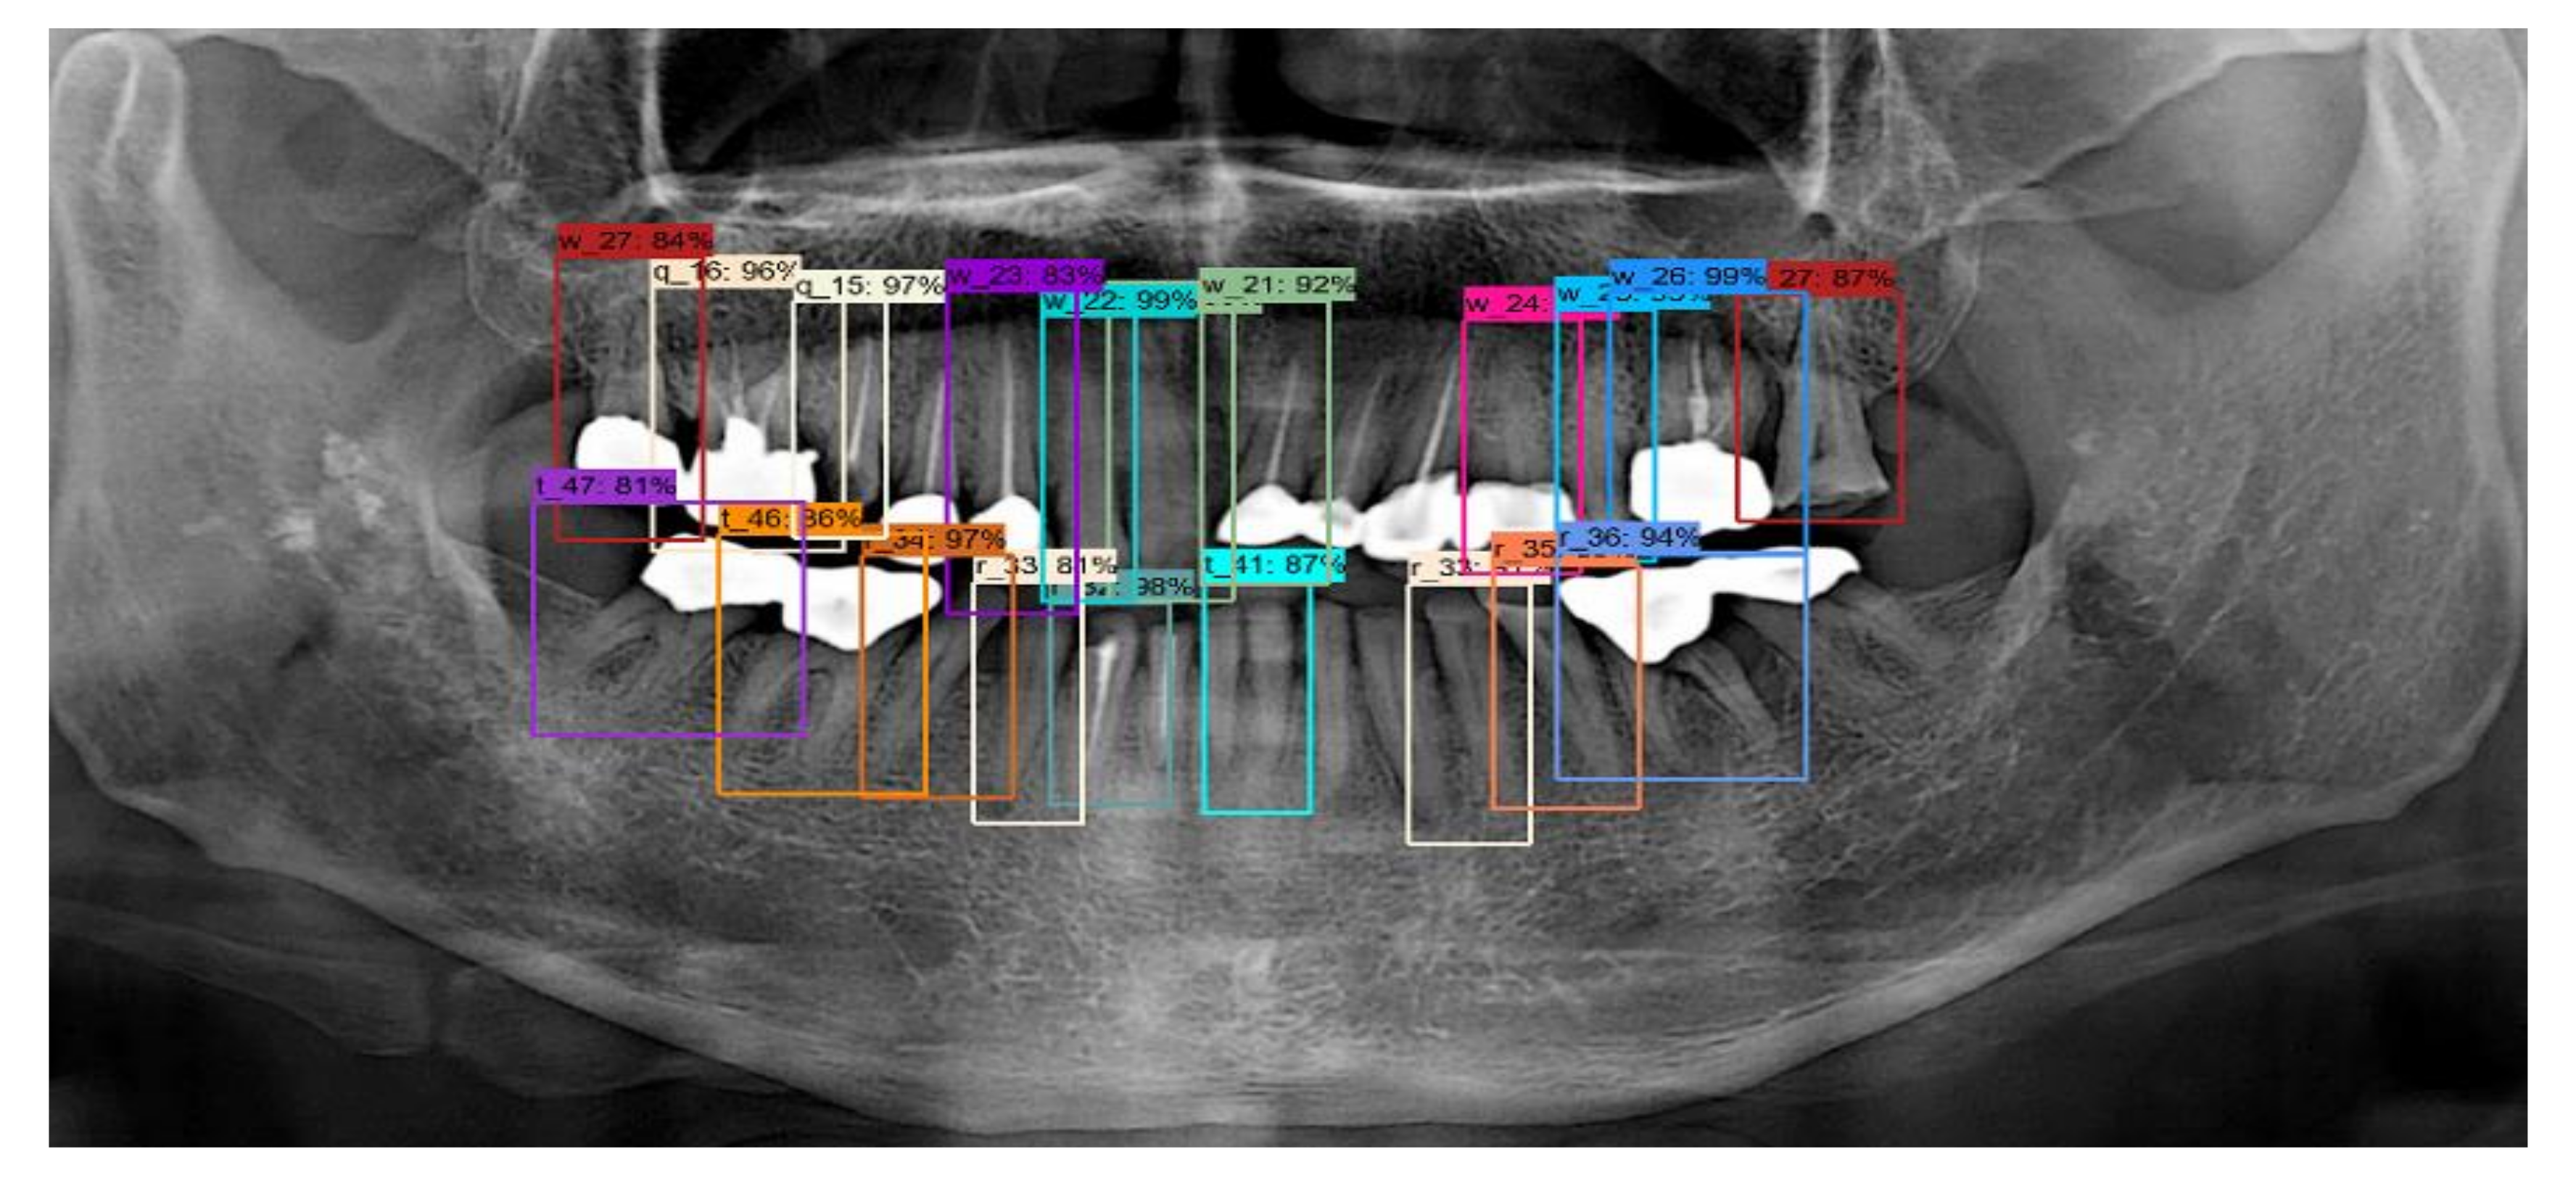

By contrast, for the case of implant fixtures and crowns, the accuracies were 45.1% and 50.9%, respectively, as shown in Table 2 when IOU = 0.5. Further, at IOU = 0.7, low accuracies of 26.6% and 40.8% were obtained for implant fixtures and crowns, respectively. These results indicate that the shapes of the implant fixtures and crowns are detected less accurately than expected. One possible reason for this is that the crowns and implant fixtures have various unstructured shapes, and hence the model may be unable to accurately detect the shapes when compared to normal teeth. Nevertheless, the results obtained are significant because the implant fixtures and crowns were still detected through the panoramic images. Therefore, as shown in Figure 9, each tooth, implant, and crown can be detected. As described above, the numbering of the teeth, the implant, and the crown is determined by detecting the teeth.

Table 3 shows that the probability of a tooth actually existing in the location indicated by the RCNN algorithm was 84.2%, with a sensitivity of 75.5%, and a precision of 84.5%. In addition, for tooth numbering, an accuracy of 77.4% was consistently obtained between the location of the actual tooth and the location indicated by the algorithms. The results of tooth detection are shown in Figure 10. As shown in this figure, all information about the position of the tooth can be detected correctly. However, it can be seen that the small tooth and crown cannot be detected for the tooth whose shape is not recognized.

Figure 9. (a) Example of tooth, (b) crown, and (c) implant fixture detection.

Figure 10. Results of tooth detection.